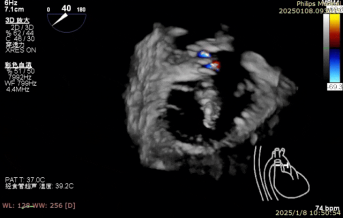

术中房间隔穿刺

术中二尖瓣夹系统瓣上调整